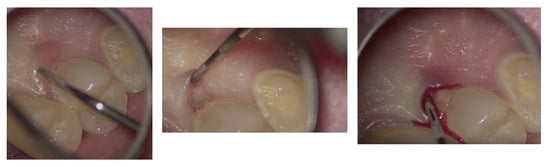

Figure 6.

Microscopic exploration and probing of EPL under the operating microscope.

The entire procedure was performed under an operating microscope, Zumax 2380®, with an integrated HP camera (Zumax Medical Co., Ltd., Suzhou, China). In this case, the endodontic access cavity was prepared using a minimally invasive approach, aiming to preserve as much dental tissue as possible while ensuring adequate control and access to both the root canals and the cervical resorption lesion (Figure 6 and Figure 7).

In agreement with the patient and accompanying family members, and after consultation with the treating oncologist, the least invasive treatment approach was chosen. After a thorough scaling procedure aimed at improving oral hygiene, the procedure was initiated under plexus anesthesia and with isolation of the operative field, taking care to minimize trauma when manipulating tissues with the hook.